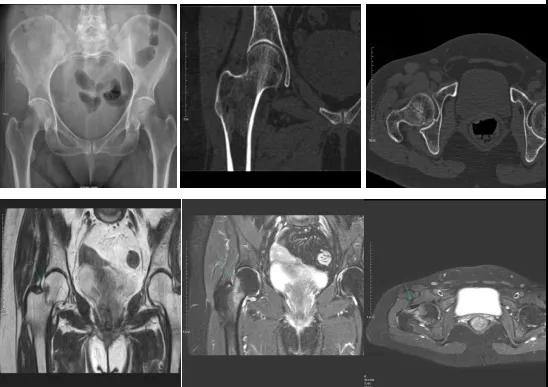

DR示:右側(cè)股骨頸未見(jiàn)明顯骨折征象。CT右側(cè)股骨頸骨質(zhì)密度不均?;颊唧w征明顯,為明確診斷,行MRI檢查。MRI示:右側(cè)股骨頸T1WI呈低信號(hào),脂肪抑制序列呈高信號(hào);提示右側(cè)股骨頸隱匿性骨折。

2.CT或MRI檢查。CT是斷面成像,不會(huì)出現(xiàn)重疊而導(dǎo)致漏診,同時(shí)CT還可以進(jìn)行多平面的重建,除了發(fā)現(xiàn)X線無(wú)法發(fā)現(xiàn)的骨折外,還可以三維直觀的顯示骨折的程度,對(duì)臨床治療有指導(dǎo)意義。CT無(wú)法發(fā)現(xiàn)骨裂、不全骨折或者骨挫傷,對(duì)軟組織的損傷診斷也有局限性,MRI就可以發(fā)現(xiàn)這些損傷。